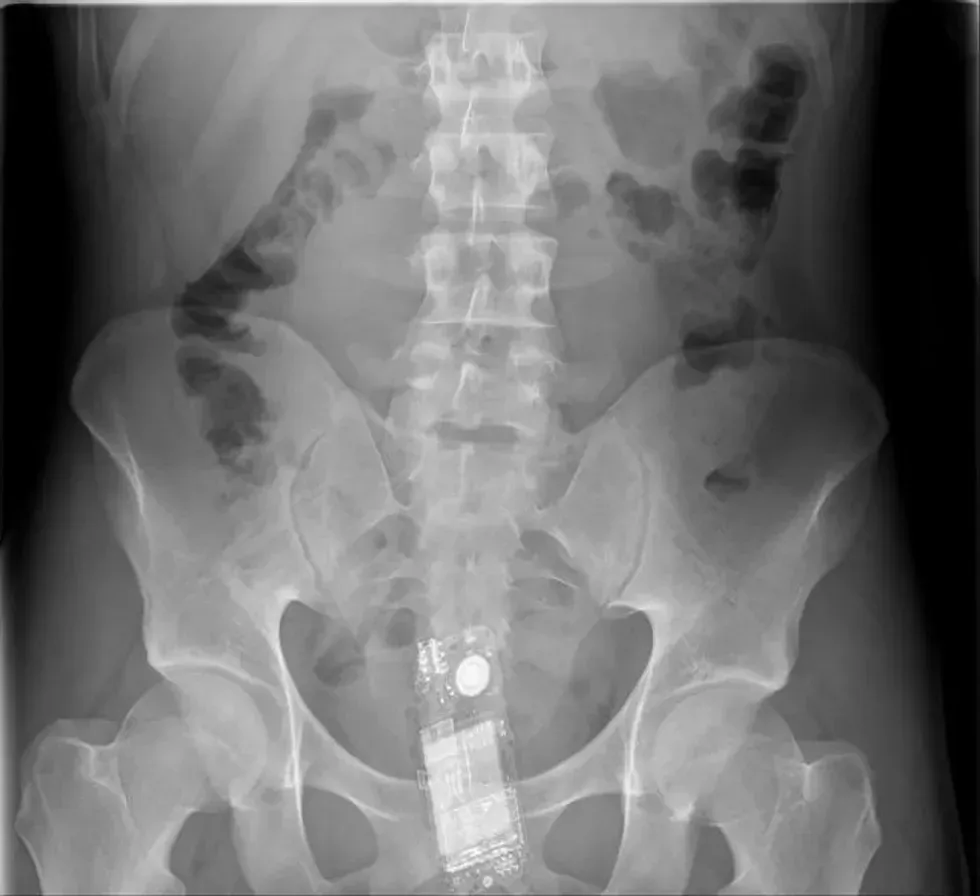

13. A shampoo bottle